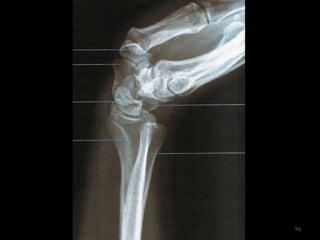

Incidência lateral cotovelo (látero-medial)65

66

67